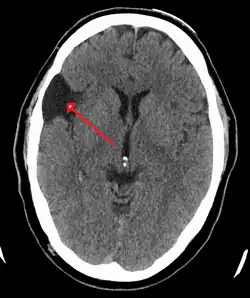

| An MRI of a 25-year-old woman with left frontotemporal arachnoid cyst. | |